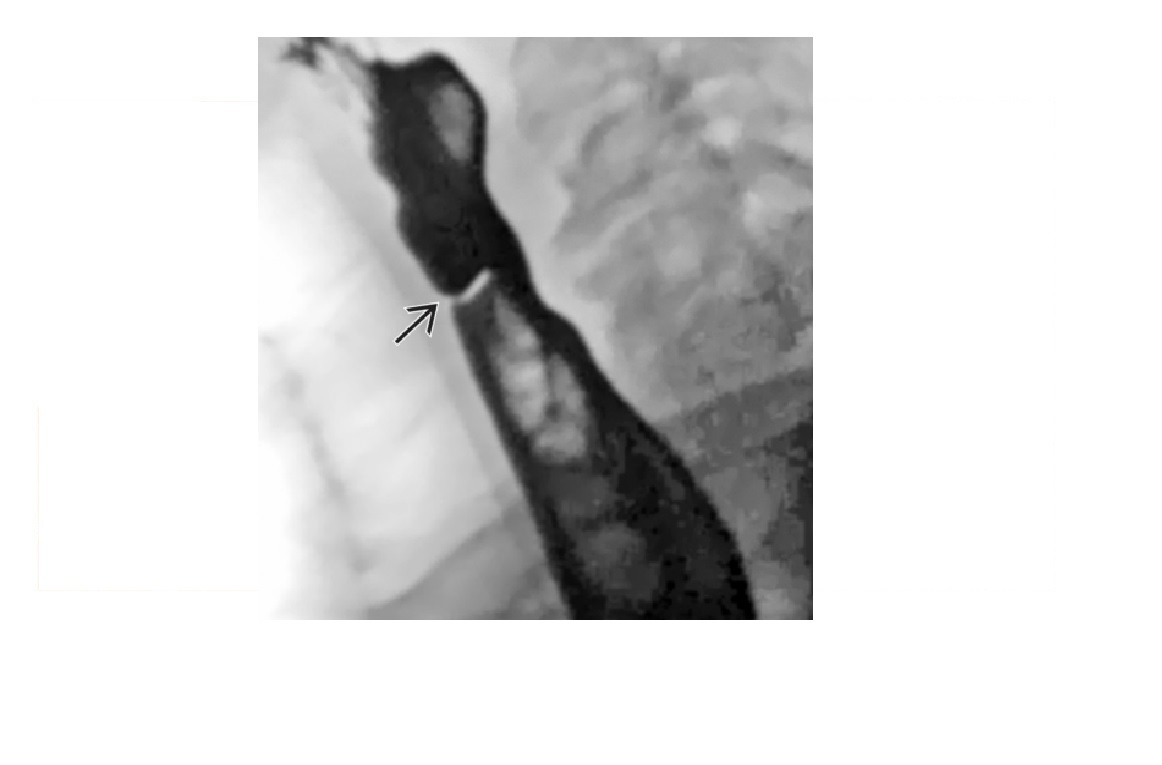

-affects the Lower 2/3 (smooth muscle) with atony and peristalsis that begin caudally and moves cranially.

-Moderate dilatation of esophagus with fusiform stricture at lower end

Nb upper 1/3 to above aortic arch is normal (striated muscle)

Achalsia

- Grossly dilated whole oesophagus with smooth, beak-like tapering at lower end

Reflux Esophagitis (With Stricture)

-Longer tapered distal stricture

-Less luminal dilation

-Distinguished from scleroderma by normal peristalsis

Esophageal Carcinoma

-Abrupt proximal borders of strictured segment (rat tail appearance)

-Mucosal irregularity, shouldering, mass effect